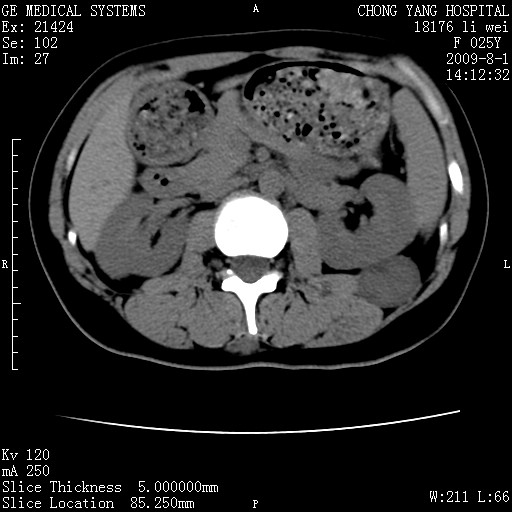

以下是引用pujunzhi在2009-8-1 20:23:00的发言:[br]胸椎旁及背部肌间良性病变,范围广,边界清,沿肌间生长,考虑淋巴管瘤、血管瘤,建议增强扫描。

以下是引用拾荒者在2009-12-30 21:45:00的发言:[br]ct21383:神经纤维瘤病( nf) [br] [br] 神经纤维瘤病。四肢都有,影响美观,四肢上的手术了。[br] [br] [br]谢谢!